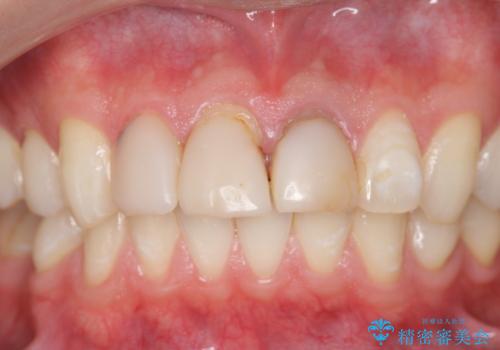

- 前歯の変色や形態を含む、見た目を改善したいと希望され来院されました。

・歯の変色 →ジルコニアクラウンの製作

・歯肉縁下カリエス →部分矯正による歯の挺出・歯周外科